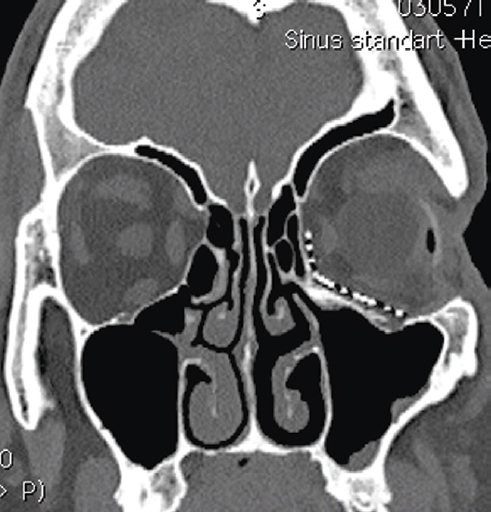

Fig. 2. Patient, 50 у.о. Multispiral computed tomography before surgery. Front view. Posttraumatic deformity of the inferior and the temporal walls of the left orbit. Increased socket volume / Рис. 2. Пациент, 50 лет. Мультиспиральная компьютерная томография до операции. Фронтальный вид. Посттравматическая деформация нижней и наружной стенок левой орбиты с увеличением объёма глазницы